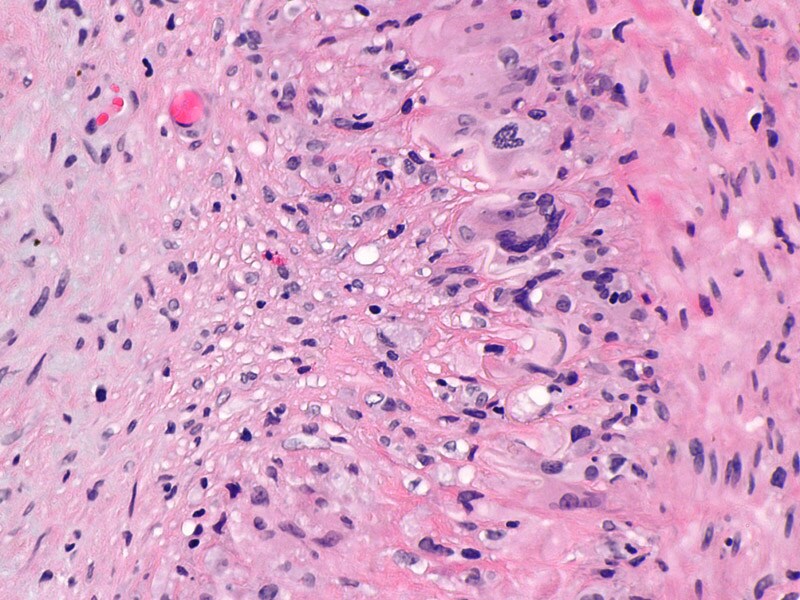

Межуточный миокардит: гистологические исследования